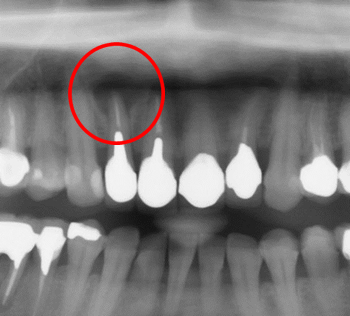

治療前

赤丸の前歯の腫れとお痛みが取れず,近歯科を受診しましたが、抜歯しないといけないといわれ当院を受診しました。患者さんはできるだけ歯を抜きたくないと強い希望がありました。

X線写真です。赤丸に大きな病巣があります。